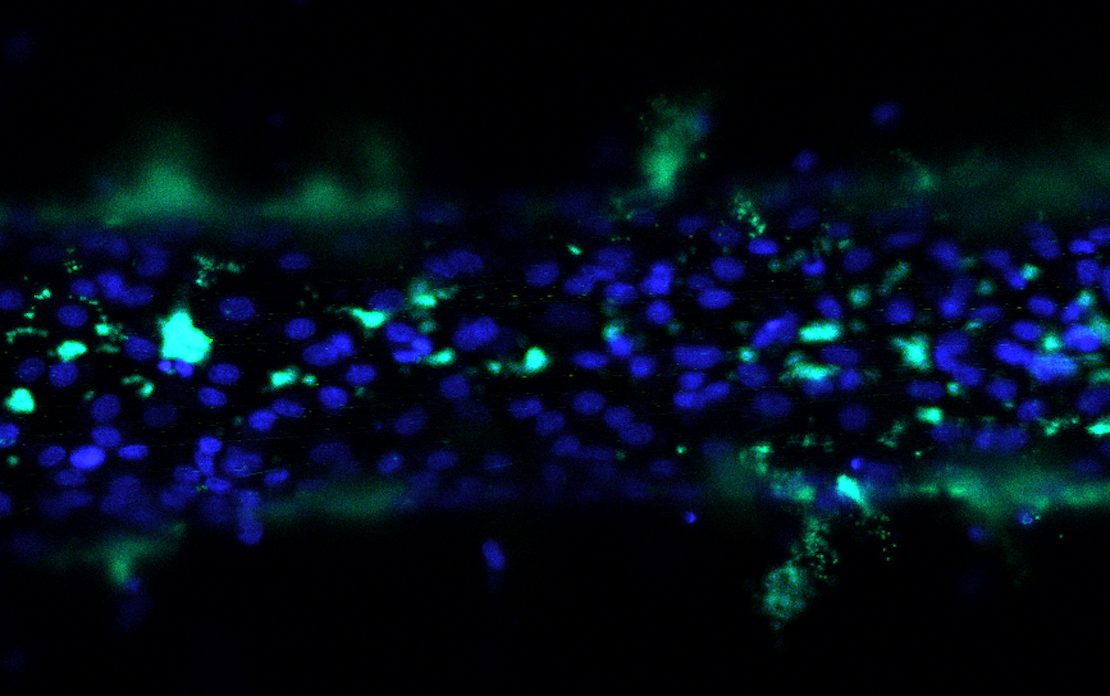

The researchers then pushed fluid through the channels and used fluorescent dye to track the resulting flow, capturing the process with a 3D confocal microscope. Their study showed the fluid particles could leak through the cell layer or get trapped in small pores.